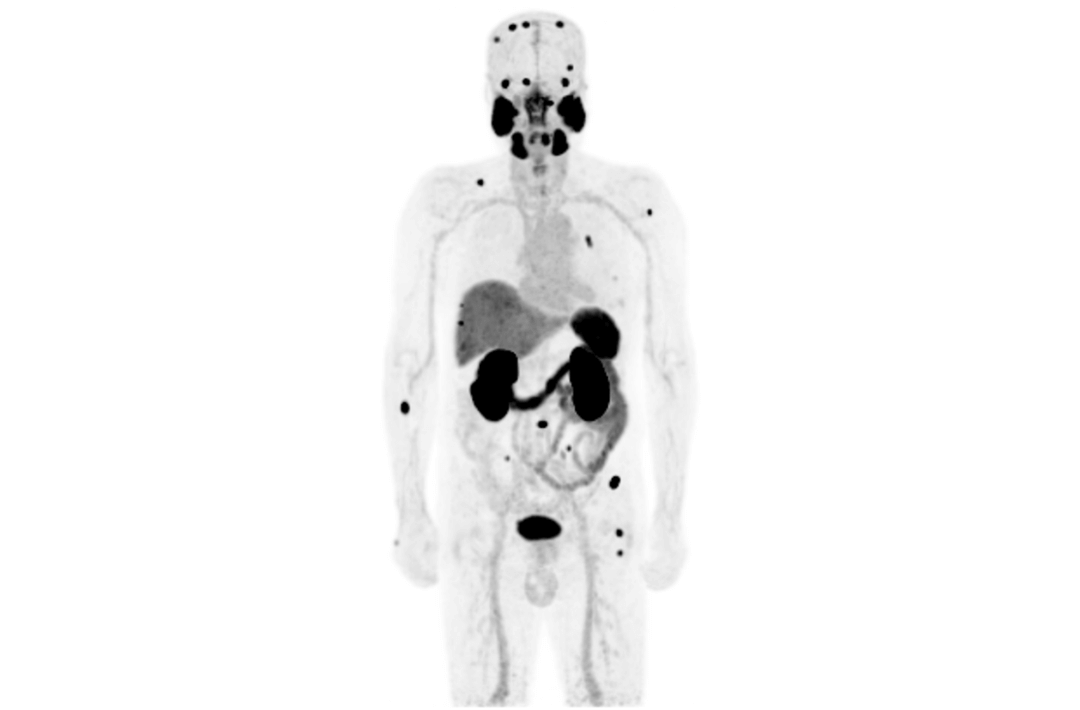

PET/MRは分子機能と構造画像を完全に結合し、腫瘍、心血管疾患、神経疾患、小児疾患、炎症性疾患の臨床診断に欠かせない手段として役立っています。

AFOVが、従来の20cm~25cmのPET装置と比較して、32cmの長尺AFOVであることにより、感度が向上するだけでなく、全身の主要臓器や転移が考えられる局所リンパ系において1ベッドポジションでがんのTNステージを実現することが可能となります。

2019年8月、Peking Cancer Hospitalはユナイテッド イメージング ヘルスケアのPET/MRを導入し、長いAFOV下でのがんTNM病期決定の徹底的な探求と最適化を行いました。500例以上の様々な臓器のスキャンにより、長い AFOV PET/MRは1つのベッドポジションでのスキャン範囲を大幅に拡大し、がんTNMステージングの効率を向上させることができることが証明されました。

乳がん、食道がん、前立腺がんなどのTNMステージングを「時空間統合」ULTRA-clear TOF PET/MRの長軸視野で最適化した事例を紹介します。